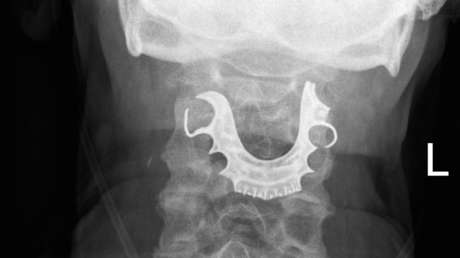

Una clínica estomatológica de la ciudad rusa de San Petersburgo exigió a uno de sus pacientes la devolución del implante dental y de las prótesis que le habían colocado previamente, comunica un bufete local de abogados en su cuenta de Facebook.

Anteriormente, el paciente, no conforme con la calidad del implante que le pusieron, demandó a la clínica. Un tribunal falló a su favor y ordenó al centro médico pagarle una indemnización de 920.000 rublos (unos 11.700 dólares).

Más tarde, el consultorio decidió tomar represalias por vías legales y exigió la devolución de los accesorios ortopédicos, así como del dinero de la compensación, al considerar que se trataba de un enriquecimiento injusto. Sin embargo, este jueves el tribunal desestimó el reclamo, argumentando que esos accesorios no representan un valor de mercado para el paciente y son materiales fungibles para la prestación de los servicios de la clínica.

Además, la corte dictaminó que la indemnización pagada no constituye un enriquecimiento indebido, ya que se trata de una forma de compensar por vías legales los daños materiales y morales ocasionados al violar los derechos del consumidor.